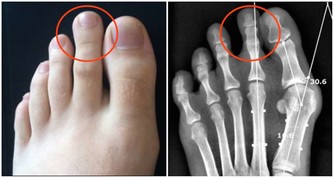

有文獻報導認為,癌細胞在增生分化過程中,會引起生長激素分泌異常。

大量的生長激素會刺激骨關節異常增生,侵犯膝、踝、腕等大關節,出現腫脹、疼痛等症狀。

據報導,老年人肺癌合併關節痛的發生率約佔10%至20%。